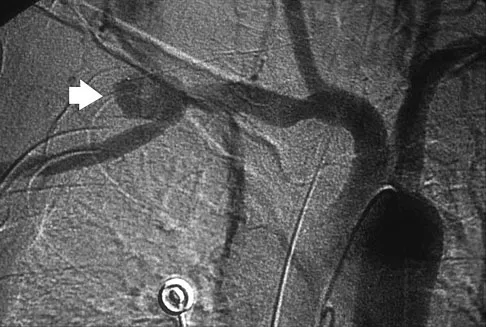

A 25-year-old man sustained a head injury after being ejected from his car. Examination reveals a Glasgow Coma Scale score of 7 and a swollen right knee. Clinical examination shows that the knee is very unstable, suggesting tears of the medial collateral and anterior and posterior cruciate ligaments, as well as the posterior lateral corner. What is the most appropriate first step to rule out a vascular injury?

Explanation